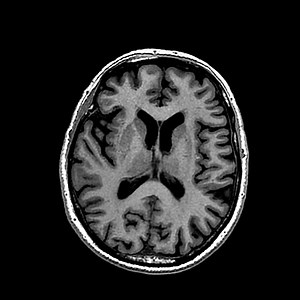

How to Start MRI Brain Step by Step

MRI Brain Scan Procedure

MRI brain scan

MRI Brain Images Explained

🧠✨ Brain MRI Sequences Explained | Radiology Essentials ✨🧠 Understanding brain MRI is all about knowing how each sequence appears and why it matters. In this video, I’ve explained the appearance and clinical importance of the most commonly used brain MRI sequences: 🔹 T1-Weighted – Best for anatomy and baseline evaluation 🔹 T2-Weighted – Highlights pathology, edema, and fluid 🔹 FLAIR – Suppresses CSF to unmask periventricular and cortical lesions 🔹 GRE / SWI – Sensitive for hemorrhage, micr